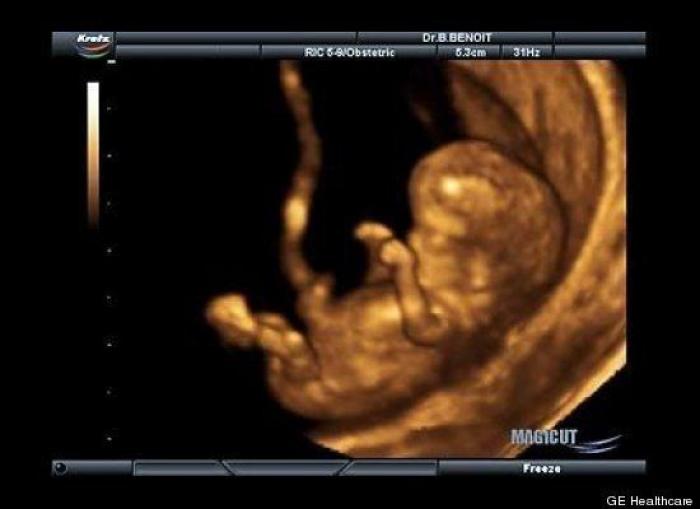

En esta galería puedes ver en fotos como es el desarrollo de un feto de semana en semana:

Desarrollo del feto, en fotos